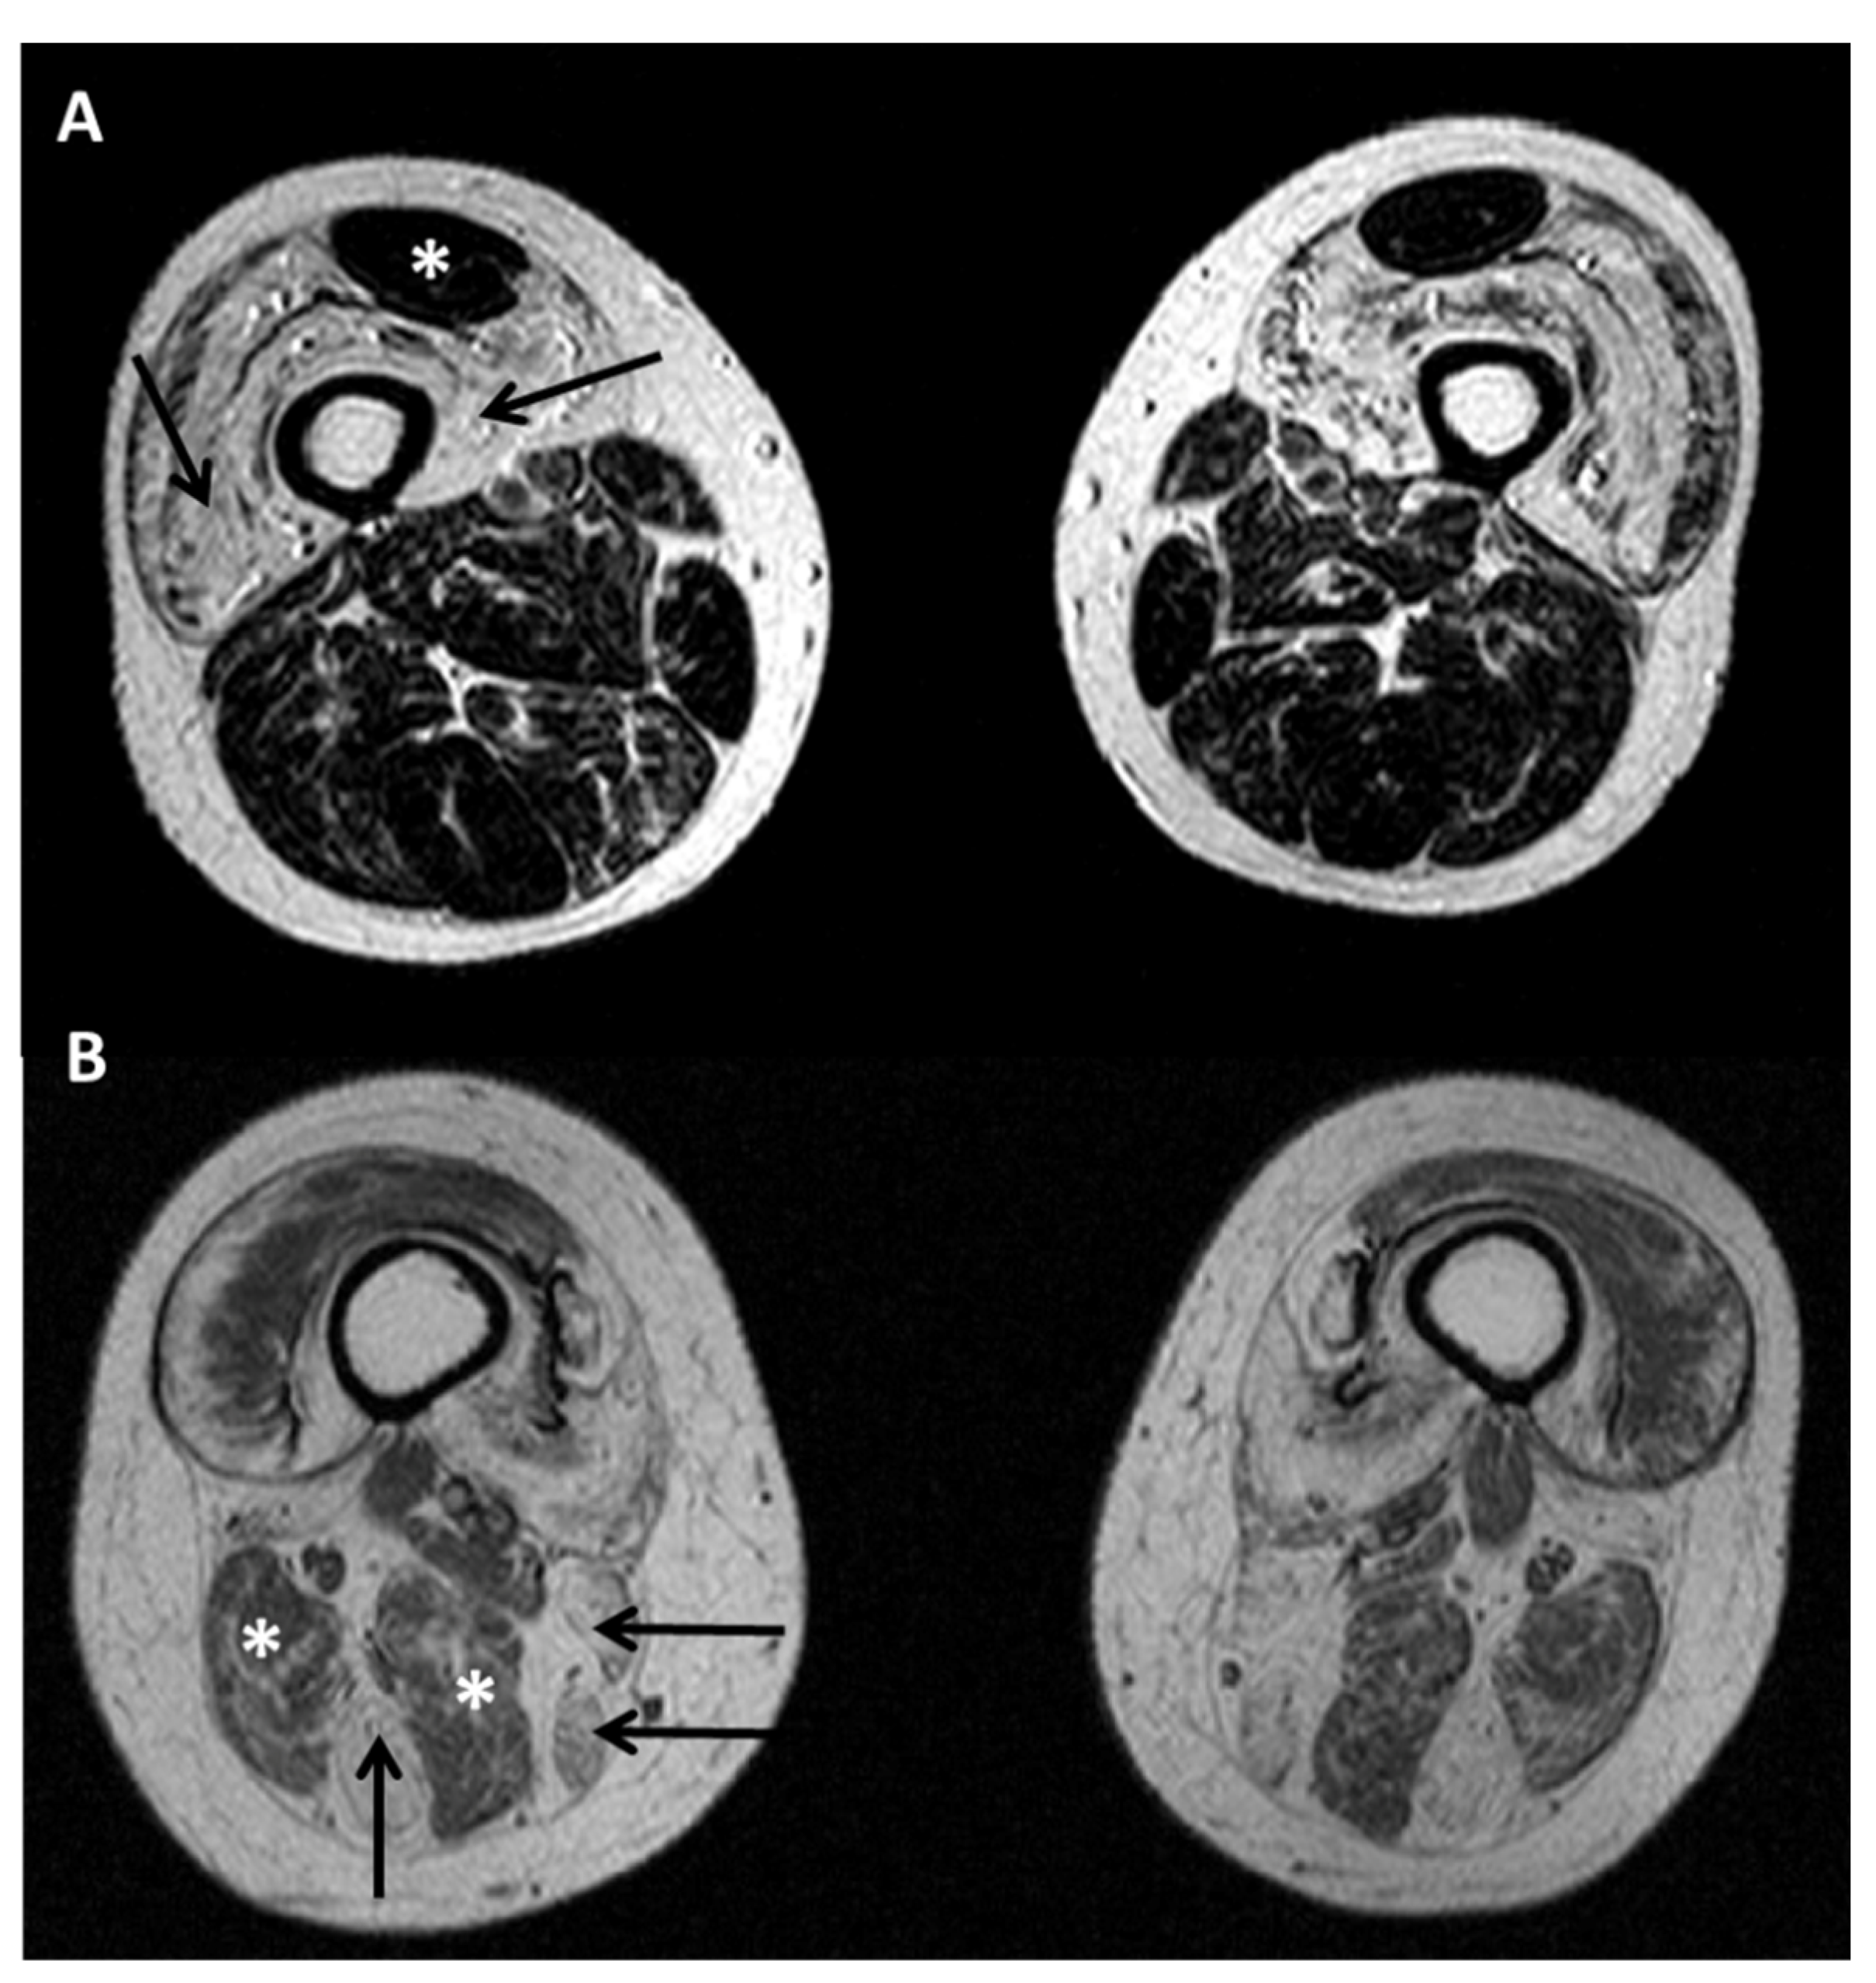

- Diaz-Manera, J.; Alejaldre, A.; Gonzalez, L.; Olive, M.; Gomez-Andres, D.; Muelas, N.; Vilchez, J.J.; Llauger, J.; Carbonell, P.; Marquez-Infante, C.; et al. Muscle imaging in muscle dystrophies produced by mutations in the EMD and LMNA genes. Neuromuscul. Disord. 2016, 26, 33–40. [Google Scholar] [CrossRef]

- Carboni, N.; Mura, M.; Marrosu, G.; Cocco, E.; Marini, S.; Solla, E.; Mateddu, A.; Maioli, M.A.; Piras, R.; Mallarini, G.; et al. Muscle imaging analogies in a cohort of patients with different clinical phenotypes caused by LMNA gene mutations. Muscle. Nerve. 2010, 41, 458–463. [Google Scholar] [CrossRef]

- Mercuri, E.; Clements, E.; Offiah, A.; Pichiecchio, A.; Vasco, G.; Bianco, F.; Berardinelli, A.; Manzur, A.; Pane, M.; Messina, S.; et al. Muscle magnetic resonance imaging involvement in muscular dystrophies with rigidity of the spine. Ann. Neurol. 2010, 67, 201–208. [Google Scholar] [CrossRef]

- Lin, H.T.; Liu, X.; Zhang, W.; Liu, J.; Zuo, Y.H.; Xiao, J.X.; Zhu, Y.; Yuan, Y.; Wang, Z.X. Muscle Magnetic Resonance Imaging in Patients with Various Clinical Subtypes of LMNA-Related Muscular Dystrophy. Chin. Med. J. 2018, 131, 1472–1479. [Google Scholar] [CrossRef] [PubMed]